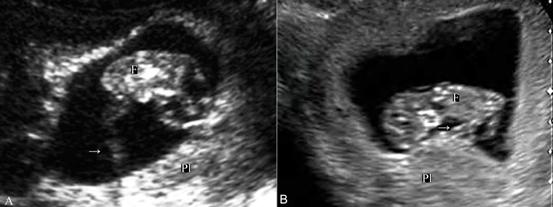

月经后第4周胎盘循环已建立,但经腹超声显像检查要在第7孕周以后、当妊娠囊其他部位的蜕膜反应形成的强回声变薄后才能在妊娠囊一侧显示局限性增厚及密集回声的胎盘。早期的胎盘面积多较大,可以占据子宫腔的1/2~1/3以上;第9孕周~10孕周以后可显示典型的胎盘回声,边缘清晰可认。正常胎盘显示为新月形、弥漫性均匀一致的中等强度回声。胎盘与胎体之间的脐带显示为绳索状回声,漂浮在羊水内。由于脐带较细,多数于早期妊娠过程中常规超声显像检查显示不清,彩色多普勒血流显像检查可以脐带的血流(图2,3)。

图2 早孕期脐带[A:9周胎儿脐带声像图(→); B:11周胎儿脐带回声(→)]

图2 早孕期脐带[C:11周胎儿脐带游离段血流(→);D:11周胎儿体内脐静脉(→)及脐动脉血流(↑